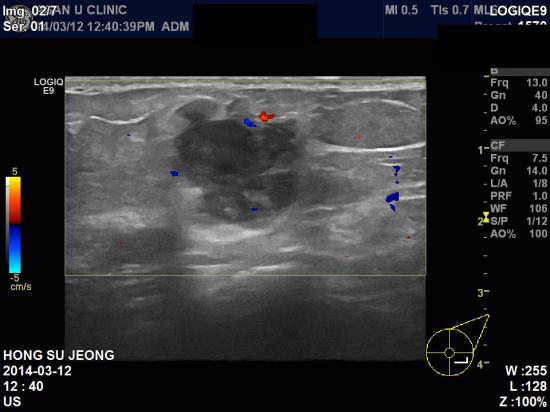

아산유외과 진료 후 74번째 유방암진단.

2~3일전부터 좌측가슴에 멍우리가 만져지는것 같다고 하시며

내원하신54세 여자분이십니다.

촉진상에도 살짝 딱딱하게 느껴지는 멍우리가 만져졌고

본원 초음파 검사상 좌측유방 4시방향 젖꼭지에서 4cm 떨어진곳에 2.79 cm 의

혹이 발견되어 조직검사결과 침윤성유관암으로 진단되었습니다.

아마 이 혹은 2~3일전이아닌 몇달전부터 만져졌을 가능성이 큽니다.

내 몸에 관심을 가지고 꾸준히 관찰할 필요가 있습니다.